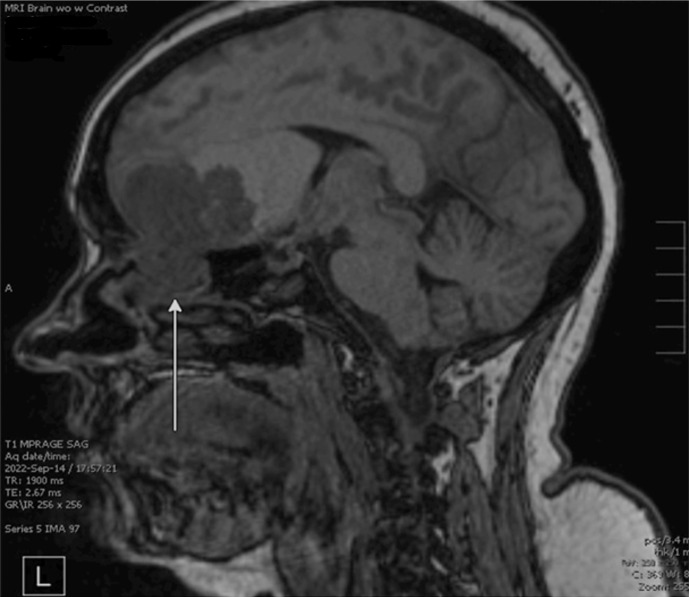

Case presentation: We report a case of a 48-year-old female patient who presented with headache, nausea, and vomiting. Initial imaging revealed a 6.4 × 4.5 cm extra-axial mass in the right frontal region, originating from the superior right nasal cavity. She underwent surgical resection of the tumor and was found to have SNTCS. She received concurrent chemoradiotherapy. Next-generation sequencing showed mutations in the PTEN, SMARCA4, and CCND1 genes. Six months after completion of treatment, she experienced an aggressive leptomeningeal recurrence of her disease. To our knowledge, our case represents the first SNTCS case with a documented PTEN mutation. In the absence of evidence-based guidelines due to the rarity of this diagnosis, we have reviewed over 50 cases reported in the literature.